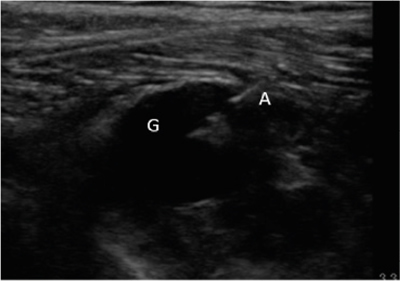

Neuropatía peronea secundaria a ganglión extraneural: revisión de literatura y propuesta de tratamiento. Caso no positivo

Este artículo presenta el caso de un paciente de 69 años con una neuropatía compresiva peronea secundaria a un ganglión, inicialmente interpretada como una radiculopatía L5. Este incorrecto enfoque supuso la sobremedicación del paciente, un mal control algésico, la realización de una discectomía L4-L5 innecesaria y una pobre evolución neurológica.

Un enfoque diagnóstico correcto y un abordaje terapéutico precoz habrían supuesto una mayor mejoría clínica e incluso una recuperación neurológica completa del paciente. Por ello, este caso sirve para resaltar: a) el valor de la ecografía en neuropatías periféricas como herramienta diagnóstica y pronóstica y el de la ecografía en gangliones como arma diagnóstico-terapéutica; b) el uso de las pruebas diagnósticas como apoyo a una exploración física exhaustiva, y no como diagnóstico en sí mismas, y c) la importancia de la publicación de casos no positivos para optimizar recursos, evitar repetir errores, reducir el sesgo de publicación y facilitar el inicio de proyectos de investigación.